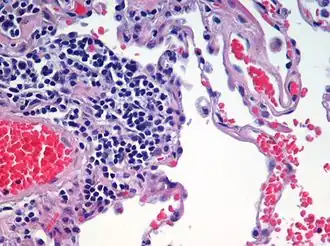

Haematoxylin and eosin (H&E)

Haematoxylin and eosin staining is frequently used in histology to examine thin tissue sections.[10] Haematoxylin stains cell nuclei blue, while eosin stains cytoplasm, connective tissue and other extracellular substances pink or red.[10] Eosin is strongly absorbed by red blood cells, colouring them bright red. In a skillfully made H&E preparation the red blood cells are almost orange, and collagen and cytoplasm (especially muscle) acquire different shades of pink.

All are used to examine blood or bone marrow samples. They are preferred over H&E for inspection of blood cells because different types of leukocytes (white blood cells) can be readily distinguished. All are also suited to examination of blood to detect blood-borne parasites such as malaria.[14]